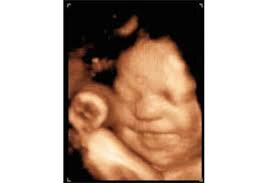

• Semana 11

Semana 11

El feto se mueve y responde al contacto (cuando percibe la presión a través del abdomen de la madre).

El embrión mide 4,2 cm